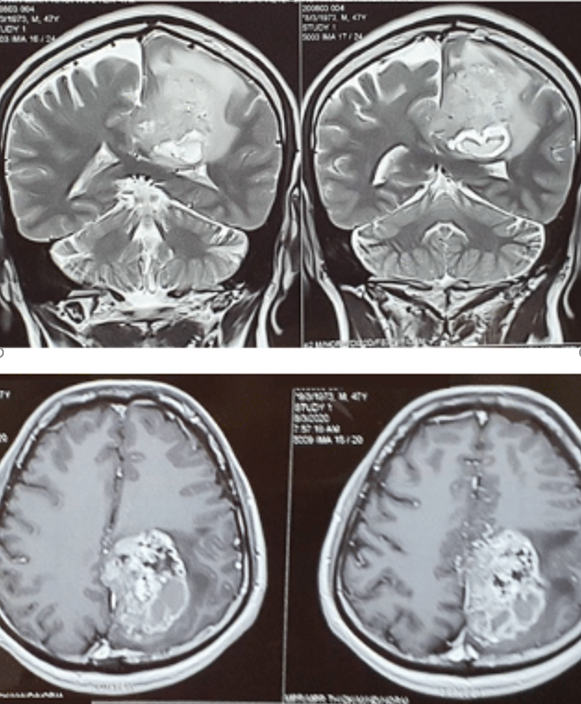

Đau đầu nguy hiểm không thường gặp nhưng cần được nhận diện sớm

Đau đầu kèm mờ mắt nhanh ở một bệnh nhân nữ trong 07 ngày. Được chẩn đoán U nào thùy trán Đau đầu cấp tính do tắc mạch máu não ở bệnh nhân nam 49 tuổi, có tiền căn Tăng huyết áp Đau đầu…